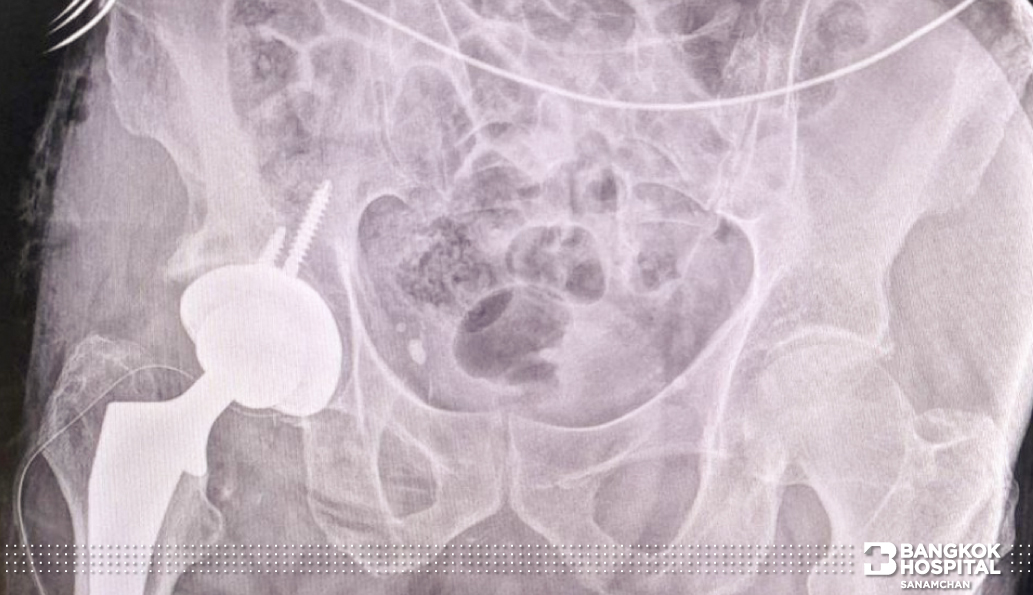

ในวันที่ผู้ป่วยได้รับการผ่าตัดเปลี่ยนข้อสะโพก ก็มีทีมแพทย์ศัลยแพทย์กระดูกและข้อ โรงพยาบาลกรุงเทพสนามจันทร์ ร่วมกับ ศัลยแพทย์กระดูกและข้อ จากโรงพยาบาลกรุงเทพ (สำนักงานใหญ่) ให้การดูแลและวางแผนการรักษา โดยในการผ่าตัดในครั้งนี้ใช้เทคนิคการผ่าตัดแบบ Direct Anterior Approach Cosmetic Incision Hip Replacement คือการผ่าตัดข้อสะโพกตามแนวบิกินี่แบบซ่อนแผลผ่าตัด ที่มีข้อดีกับตัวผู้ป่วยคือ เจ็บน้อย ฟื้นตัวไว เคลื่อนไหวสะดวก และ ลดแผลเป็น

การผ่าตัดข้อสะโพกแบบซ่อนแผลผ่าตัด